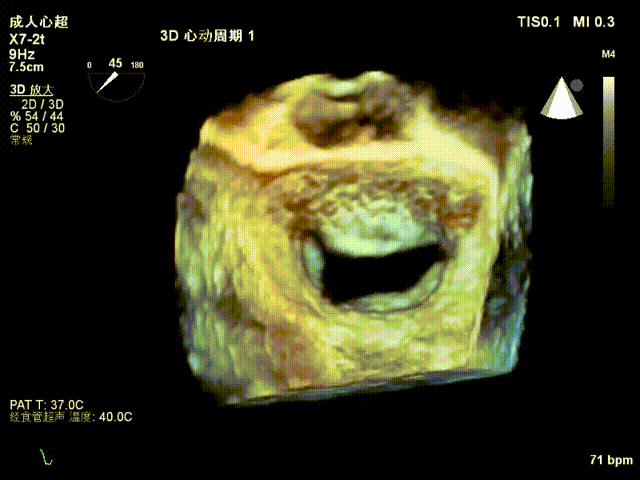

术前TEE显示重度功能性二尖瓣反流,反流位于A2/P2;

术后超声评估

术后TEE显示二尖瓣双孔化形成,反流明显减少,瓣膜夹位置稳定,二尖瓣跨瓣平均压力阶差为3mmHg,植入后反流显著下降至微量。